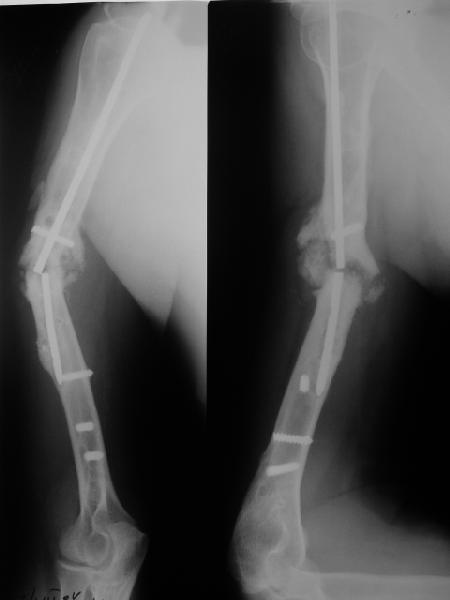

Такие надмыщелковые переломы в изолированном виде у нас в последние годы обычно фиксируются плоским титановым стержнем a la Зверев-Ключевский антеградно. Но тут еще и вышележащие проблемы.

Наверно, можно пойти на укорочение, убрав металлический цилиндр, не такой уж большой дефект. Снимки в чем-то похожего пациента прилагаю - тоже несращение диафиза после многократных операций, и надмыщелковый свежий перелом (случился после удаления обломка стержня аппарата).

Конечно, пьянство с падениями и прочими упражнениями ставит под вопрос любое дальнейшее лечение. Аппарат, что ли, еще и поверх наложить... В качестве внешнего металличкеского каркаса...